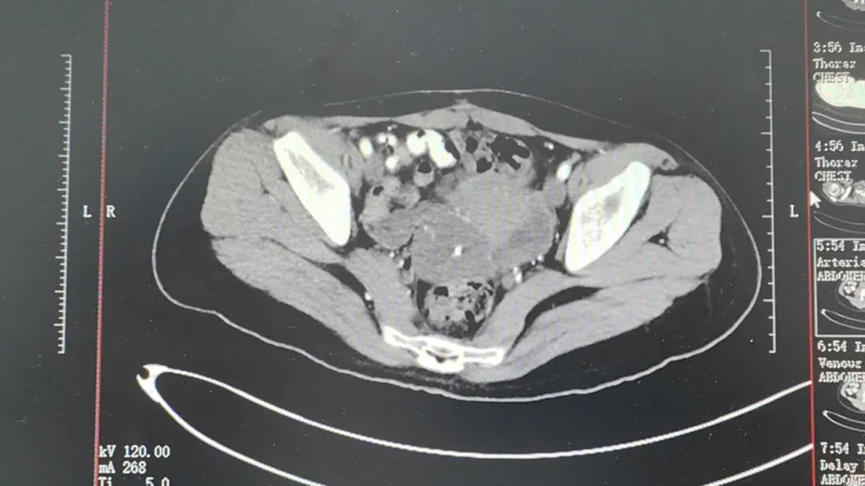

เมื่อเข้ารับการตรวจพบว่าเสี่ยวตันมีก้อนเนื้อบริเวณส่วนหลังด้านขวาของมดลูก โดยมีขอบเขตไม่ชัดเจนระหว่างมดลูก ลำไส้ตรง และรังไข่ด้านขวา จากผลตรวจการถ่ายภาพ มีแนวโน้มว่าจะเป็นเนื้องอกธรรมดา แต่น่าเสียตายที่ผลตรวจทางพยาธิวิทยาระหว่างการผ่าตัดนั้นเป็นมะเร็ง ด้วยเหตุนี้ ผู้เชี่ยวชาญจากโรงพยาบาลของเราจึงตัดสินใจใช้ วิธีการรักษาด้วยความเย็นและการฉีดยาเข้าข้างในเนื้องอกให้เธอ ซึ่งไม่เพียงแต่หลีกเลี่ยงการผ่าตัด แต่ยังช่วยให้ก้อนน้ำแข็งทำลายเนื้องอกโดยตรง ลดส่วนหนึ่งของเนื้องอก ชะลอการลุกลามของเนื้องอก และยังระงับปวดได้อีกด้วย